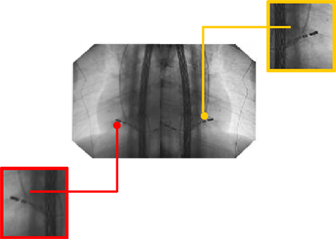

Traditionele DSA-beeldweergave

Lage schermresolutie

Onvolledige patiëntinformatie tijdens de operatie

Het beeld kan niet willekeurig worden ingezoomd of uitgezoomd

Er zijn veel schermen en de omgeving is rommelig

Displaybediening is niet handig

Afbeeldingen en vensters kunnen niet flexibel worden geconfigureerd